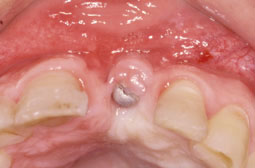

A 3 mois il ya une infection avec fistule au niveau de la 22. pour ne pas compromettre l’implant nous avons procédé à une dépose prématurée de la membrane (fig. 5-6).

Après cicatrisation nous avons constaté un déficit tissulaire vertical et horizontal, ce qui va entraîner un déficit esthétique et une dysharmonie entre les 2 incisives (fig. 7-8).